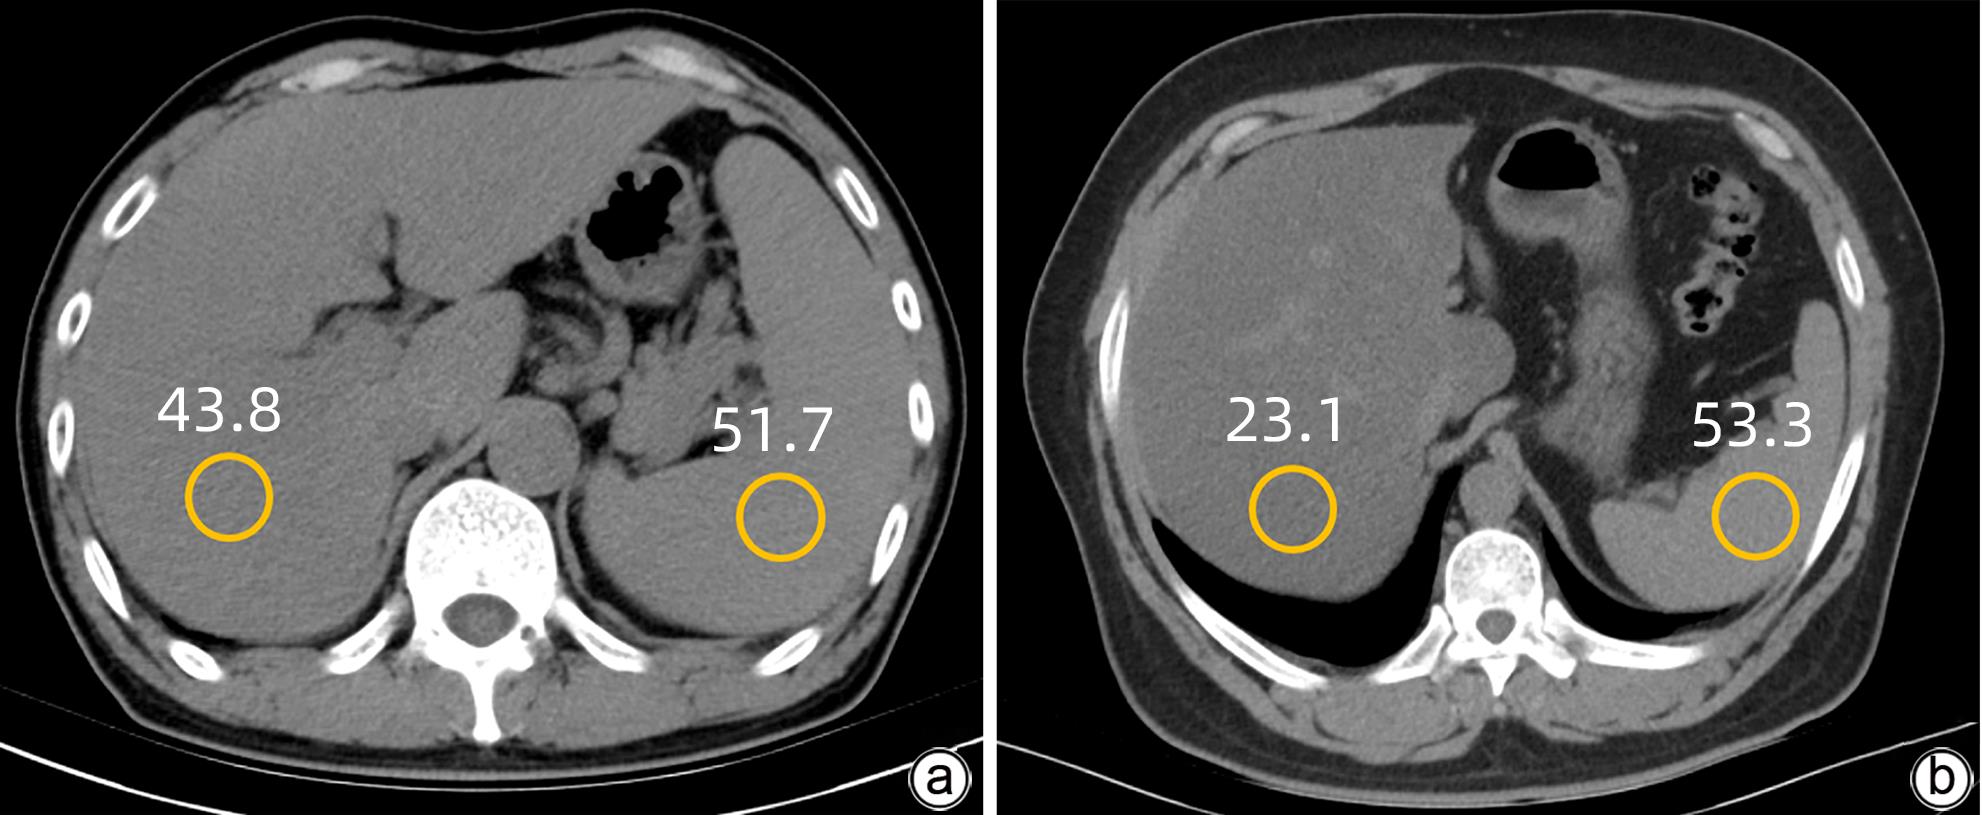

Application value of liver/spleen CT value, controlled attenuation parameter, and magnetic resonance imaging-proton density fat fraction in chronic hepatitis B patients with hepatic steatosis

Jingnan LU, Yansong LI, Ya WEN, Xionghui WANG, Zhaoyu QU, Jianlong LI, Wei ZHANG

2024, 40(1): 46-51. DOI: 10.12449/JCH240109

Abstract(1769) HTML (992) PDF (1052KB)(121)

Abstract:

Objective  To investigate the application value of liver/spleen CT value (CTL/S), controlled attenuation parameter (CAP), and magnetic resonance imaging-proton density fat fraction (MRI-PDFF) in chronic hepatitis B (CHB) patients with hepatic steatosis.  Methods  A retrospective analysis was performed for the clinical data of 213 CHB patients who underwent liver CT, CAP, and MRI-PDFF examinations in Affiliated Hospital of Yan’an University from October 2018 to December 2022. According to MRI-PDFF, the 213 patients were divided into CHB group with 111 patients (MRI-PDFF<5%) and CHB+hepatic steatosis group with 102 patients (MRI-PDFF≥5%), among whom there were 69 patients with mild hepatic steatosis and 33 patients with moderate to severe hepatic steatosis. The independent-samples t test was used for comparison of normally distributed continuous data between groups, and the Mann-Whitney U test was used for comparison of non-normally distributed continuous data between groups. The Bland-Altman plot was used to evaluate the consistency in MRI-PDFF measurement between two physicians. The Spearman’s correlation coefficient was used to analyze the correlation between CTL/S and MRI-PDFF and between CAP and MRI-PDFF. The receiver operating characteristic (ROC) curve was plotted and the area under the ROC curve (AUC) was calculated to investigate the value of CTL/S and CAP in the diagnosis of different degrees of hepatic steatosis, and the DeLong test was used to compare the AUCs of the two radiological examinations.  Results  MRI-PDFF had relatively high repeatability and stability in CHB patients. There is a significant negative correlation between CTL/S and MRI-PDFF (r=-0.800, P<0.001) and a significant positive correlation between CAP and MRI-PDFF (r=0.692, P<0.001). Both CTL/S and CAP had a relatively high accuracy in the diagnosis of hepatic steatosis in CHB patients, with an AUC of 0.951 and 0.902, respectively, and CTL/S had a better accuracy than CAP (P<0.05). In the diagnosis of mild and moderate-to-severe hepatic steatosis, CTL/S had an AUC of 0.921 and 0.895, respectively, and CAP had an AUC of 0.859 and 0.825, respectively, suggesting that CTL/S had a slightly higher diagnostic efficiency than CAP.  Conclusion  MRI-PDFF has high repeatability and stability in CHB patients, and CTL/S and CAP have a high diagnostic value for different degrees of hepatic steatosis in CHB patients.